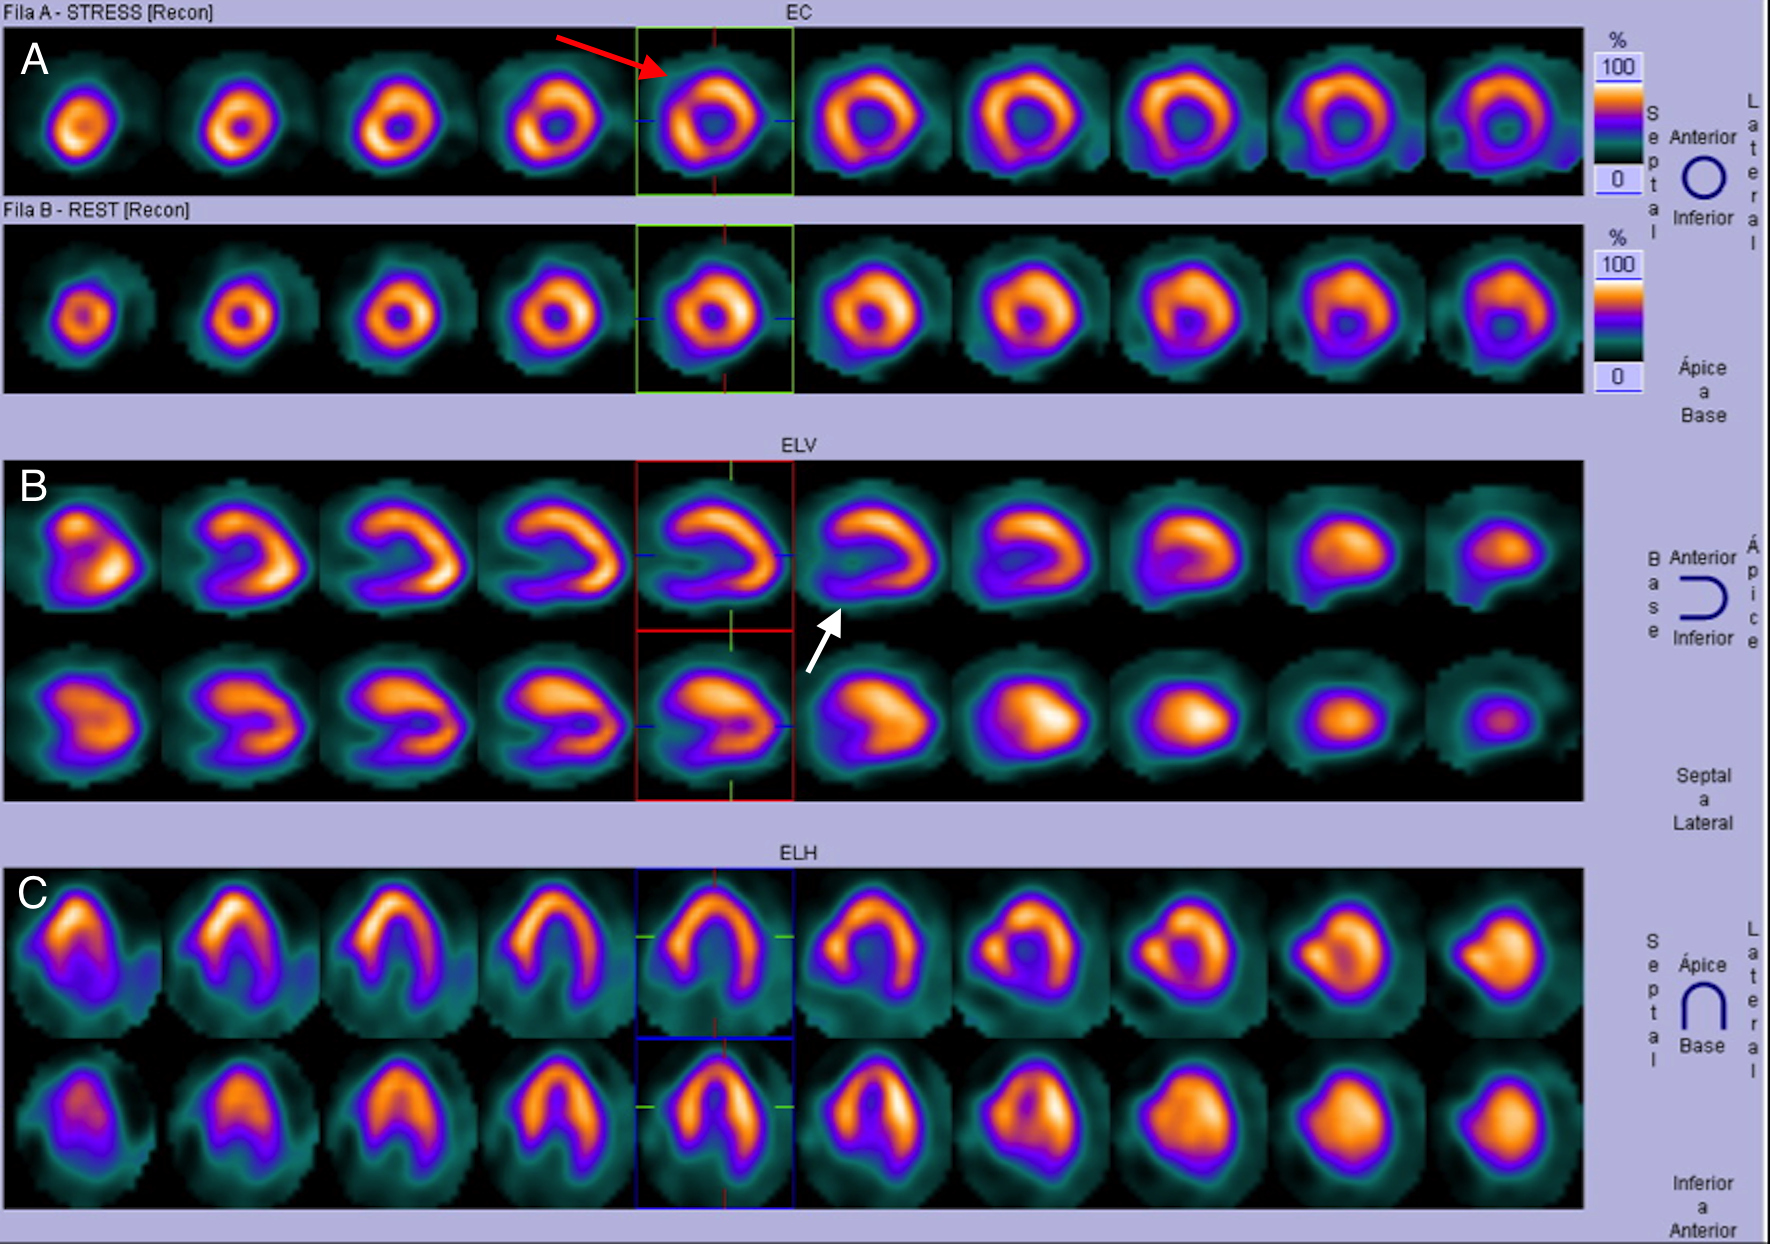

Estudio de perfusión miocárdica con 99mTc-MIBI en fases post-estrés físico y reposo. Imágenes correspondientes al eje corto (A), eje largo vertical (B) y eje largo horizontal (C) mostrando en las filas superiores las imágenes post-estrés y en las inferiores las imágenes de reposo. Existe disminución leve-moderada de la captación del 99mTc-MIBI post-estrés en el segmento medial de la región anteroseptal (flecha roja), así como en los segmentos medial y basal de la pared inferior e inferolateral (flecha blanca), todo lo cual se normaliza en reposo. Se observa además engrosamiento de las paredes del VI a predominio septal.

Ante estos hallazgos, se decidió realizar estratificación de riesgo mediante gammagrafía de perfusión miocárdica Gated-SPECT (estudio tomográfico sincronizado con electrocardiograma) con 99mTc-MIBI (dosis total 24 mCi) bajo protocolo de esfuerzo físico y reposo de 2 días. Las imágenes evidenciaron hipocaptación moderada en los segmentos basal y medial de las caras inferior e inferolateral del VI y en el segmento medial de la cara anteroseptal en el estrés, con reversión completa en el reposo. El resultado fue catalogado como isquemia inducida en los segmentos mencionados (figura 1), a lo que se asoció dilatación ventricular durante el estrés con TID (dilatación isquémica transitoria) calculada en 1,28 (valores considerados normales < 1,19) (figuras 2 y 3), fracción de eyección en el reposo de 57% que cayó a 40% post-estrés y deformidad parcial del septum basal.